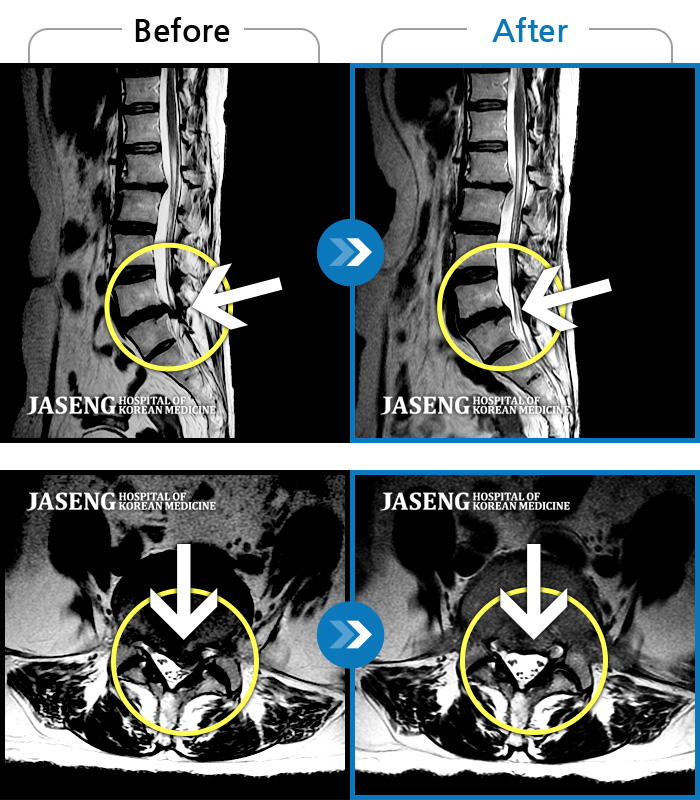

MRI 치료사례

좌측 둔부, 좌측 다리로 이어지는 통증이 심해 발을 내딛는것이 어려운 상태로 내원하신 환자분입니다.